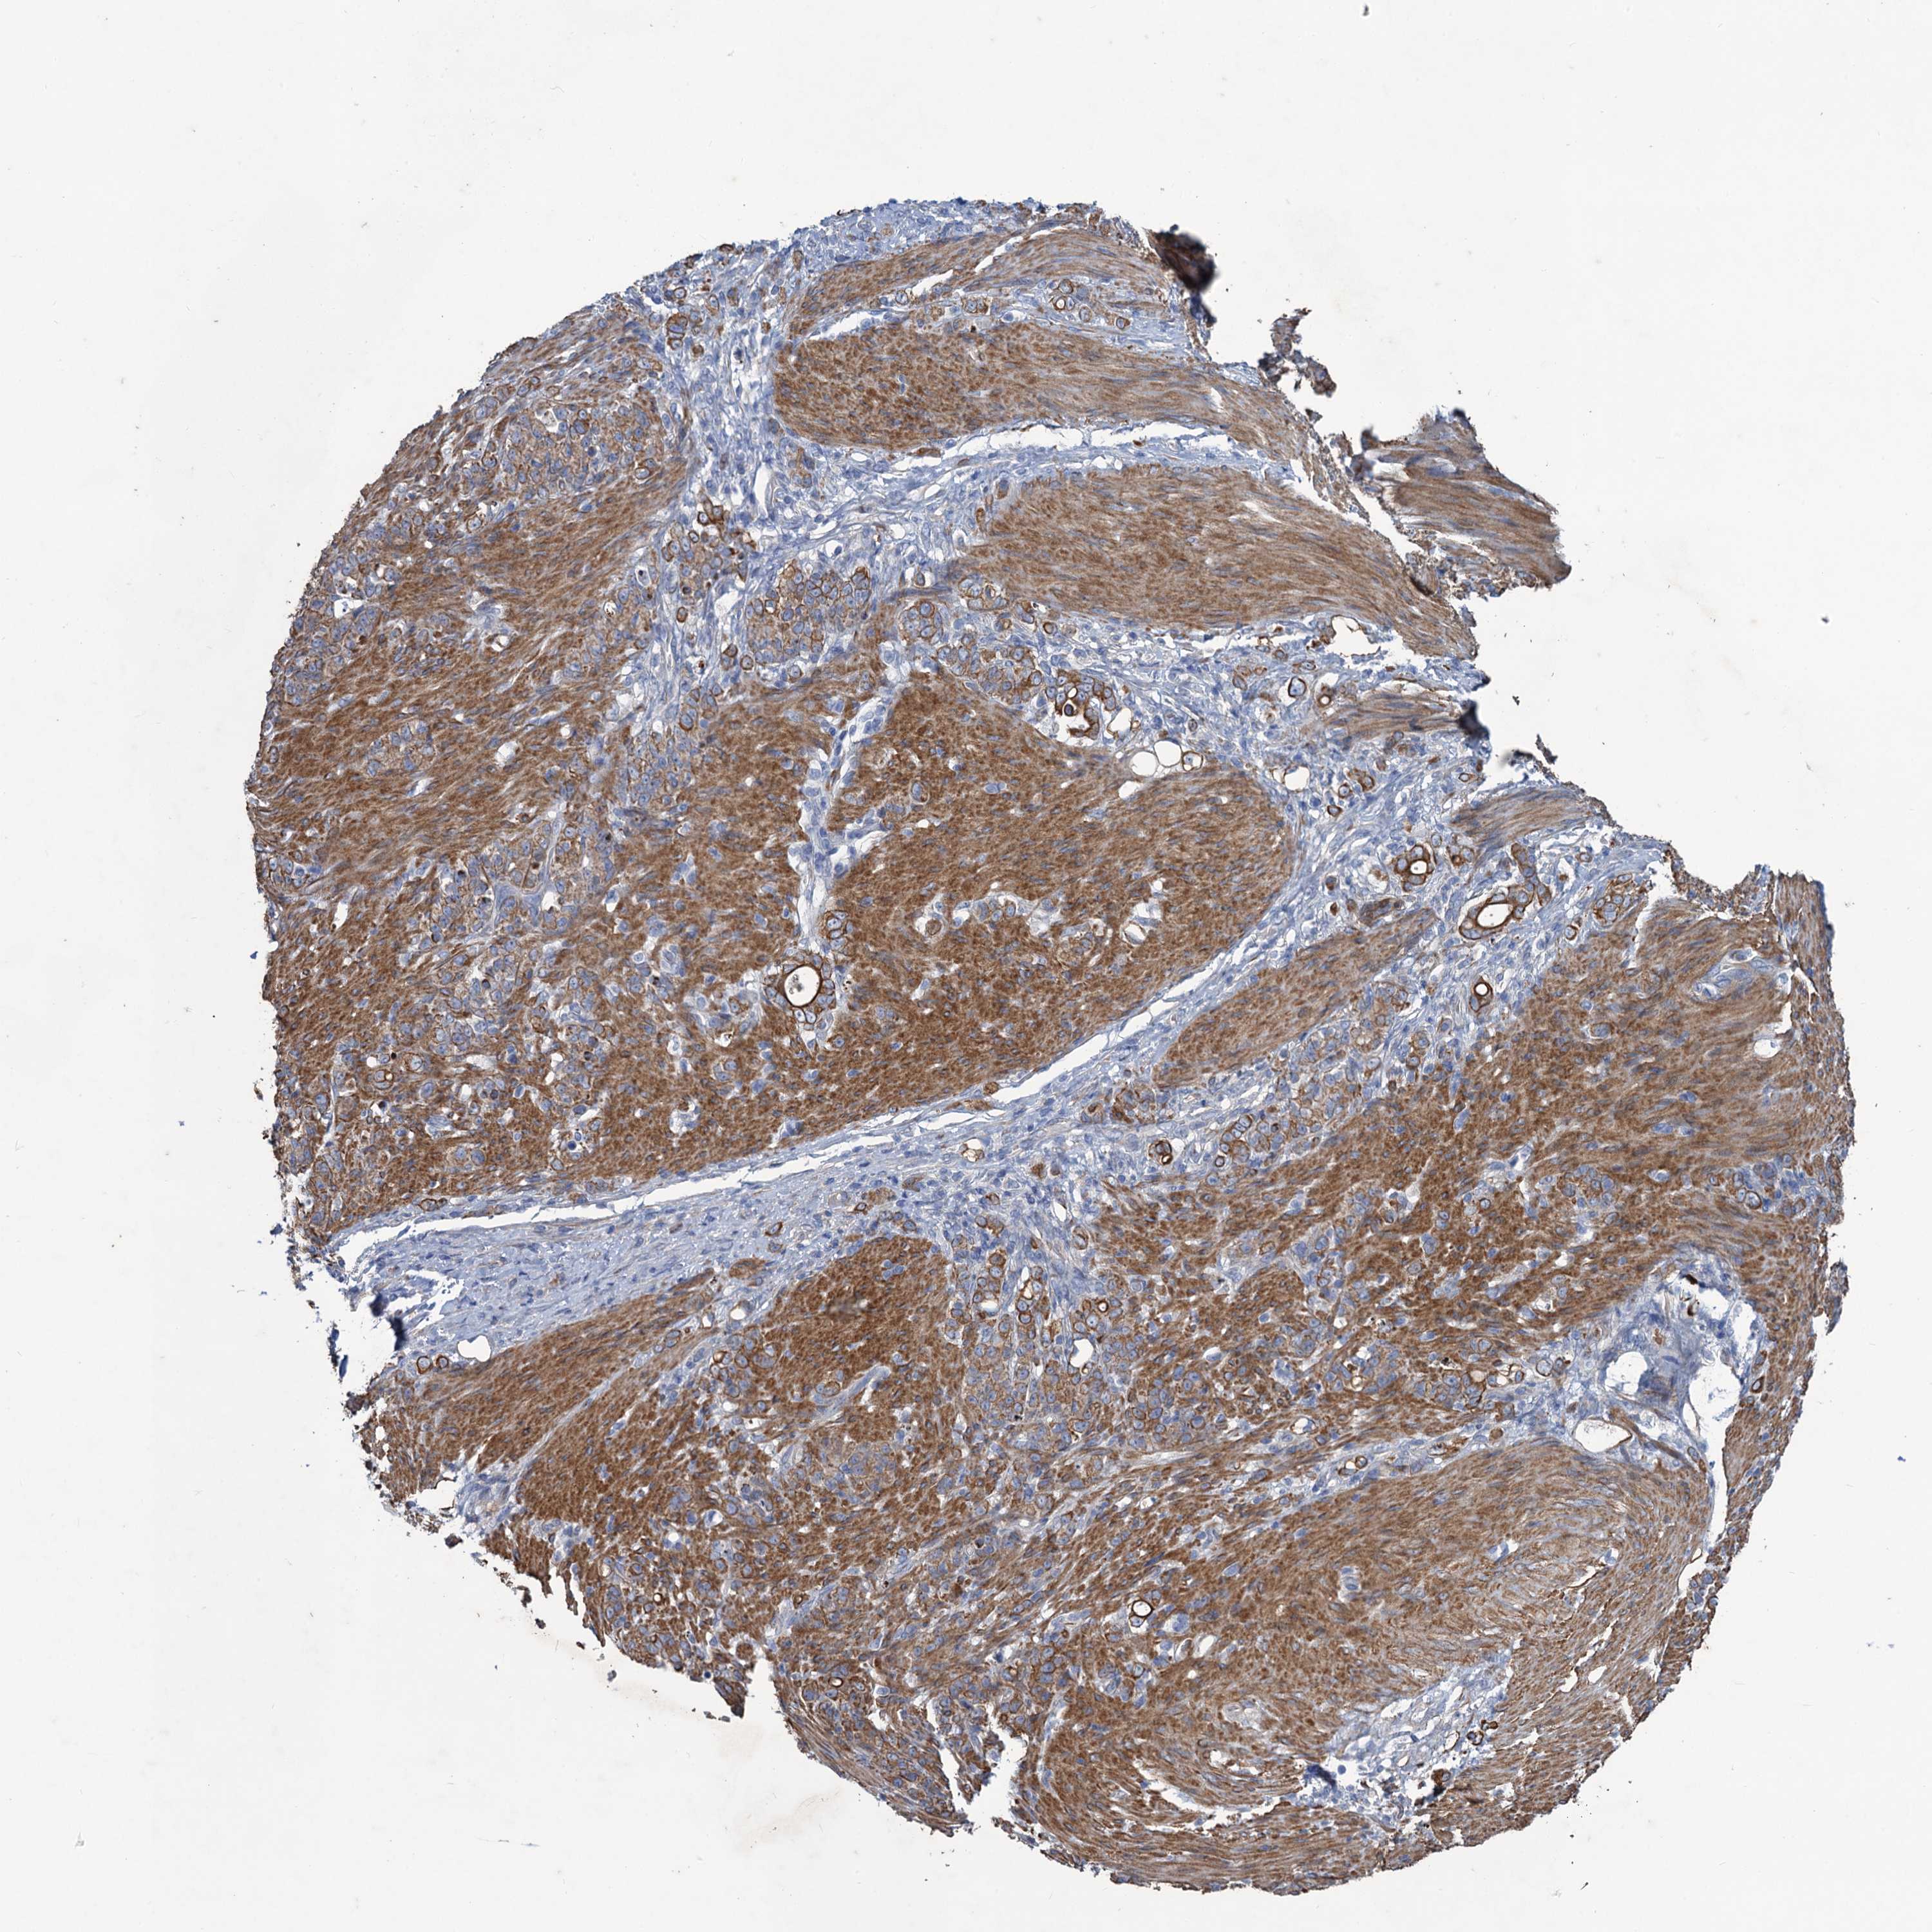

STOMACH CANCER - Protein expressioni

A mouse-over function shows sample information and annotation data. Click on an image to view it in a full screen mode. Samples can be filtered based on level of antibody staining by selecting one or several of the following categories: high, medium, low and not detected. The assay and annotation is described here.

Note that samples used for immunohistochemistry by the Human Protein Atlas do not correspond to samples in the TCGA dataset.

Antibody stainingi

Antibody staining in the annotated cell types in the current human tissue is reported as not detected, low, medium, or high, based on conventional immunohistochemistry profiling in selected tissues. This score is based on the combination of the staining intensity and fraction of stained cells.

Each image is clickable and will lead to virtual microscopy that enables deeper exploration of all samples and also displays staining intensity scores, fraction scores and subcellular localization as well as patient and tissue information for each sample.

Antibody HPA040574

Antibody HPA047804

Staining

High

Medium

Low

Not detected

Intensity

Strong

Moderate

Weak

Negative

Quantity

>75%

75%-25%

<25%

None

Location

Nuclear

Cytoplasmic/membranous

Cytoplasmic/membranous,nuclear

Adenocarcinoma, NOS

Adenocarcinoma, High grade